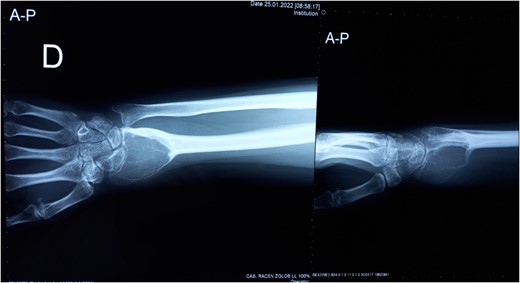

We present a case of a 32-year-old female patient who presented with pain and swelling in the area of the right wrist. On the initial X-ray, an osteolytic lesion of the distal part of the right radius was detected, highly suspicious for GCTB. Curettage of the lesion was performed and the histological examination of the specimen confirmed the previously suspected diagnosis.

Three years after the first surgery, the patient experienced pain and swelling in the area of the right wrist, highly suspicious of local tumor recurrence (Fig. 1). Due to aggressive local recurrence, in order to achieve local control of the lesion, and after Tumor Board discussion, we decided to perform wide resection of the distal radius and reconstruction with autologous vascularized fibular graft with harvestation of the inferior lateral geniculate branch and peroneal vessels.